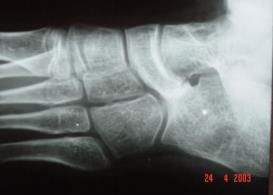

Considere a radiografia a seguir:

A imagem demonstra detalhe de radiografia do pé em incidência oblíqua mostrando alteração do contorno e do formato do osso: